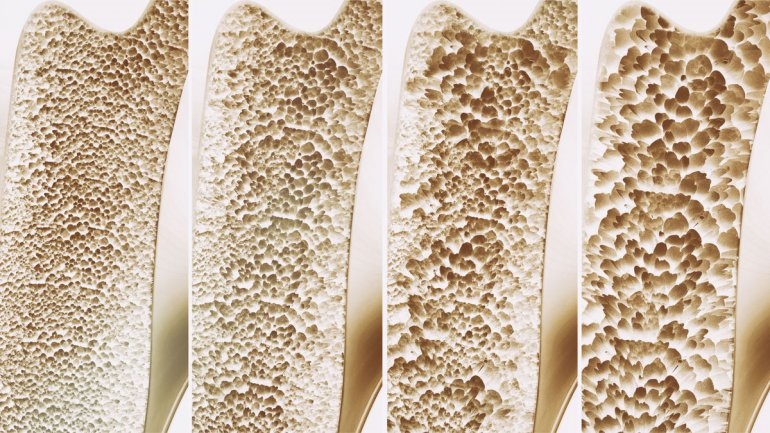

Ο περιορισμός βάδισης αυξάνει τον κίνδυνο κατάγματος

Ο περιορισμός στο περπάτημα σχετίζεται σημαντικά με τον κίνδυνο κατάγματος σε μια διάρκεια 4-5 ετών, σύμφωνα με μια μελέτη που δημοσιεύθηκε στο JAMA Network Open.